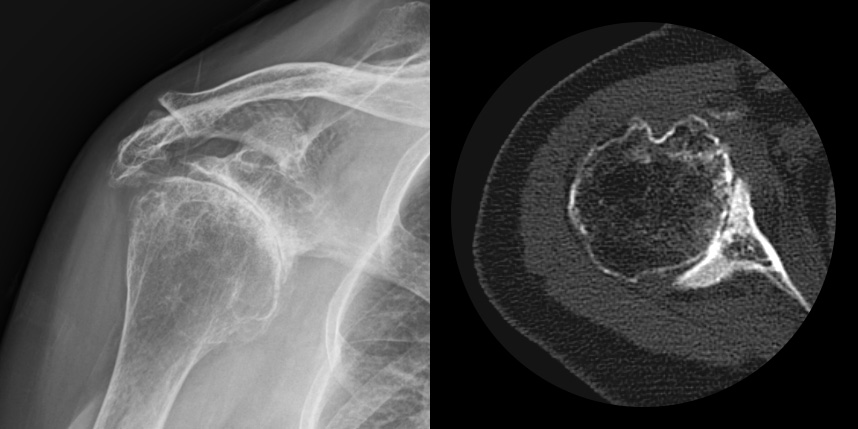

어깨 관절염이 발생하게 되면 심한 통증 및 움직임 제한으로 일상생활에 큰 영향을 받게 됩니다.

발생부위와 원인으로는 퇴생성, 골절이나 탈구 등 외상의 합병증, 류마티스, 진행된 회전근개파열, 골괴사 등에 의해 발생하게 됩니다.

주로 젊은 층에서는 외상, 류마티스 관절염, 수술 등에 의해 2차적으로, 50대 이후에는 퇴행성으로 생기게 됩니다.

어깨 퇴행성은 많이 써서 닳고 노화에 따른 변화가 생긴 것으로, 말 그대로 어깨가 많이 사용되면서 연골이 닳아서

마모돼어 생기는 관절염입니다. 어깨 회전근개 관절병증 원인으로는 어깨 힘줄 파열을 방치했을 때 관절이 틀어진 상태에서 계속

사용하게 되면 관절이 많이 상해서 관절염까지 진행되며, 이런 경우 회전근개파열의 결과로 생긴 관절병이라고 합니다.